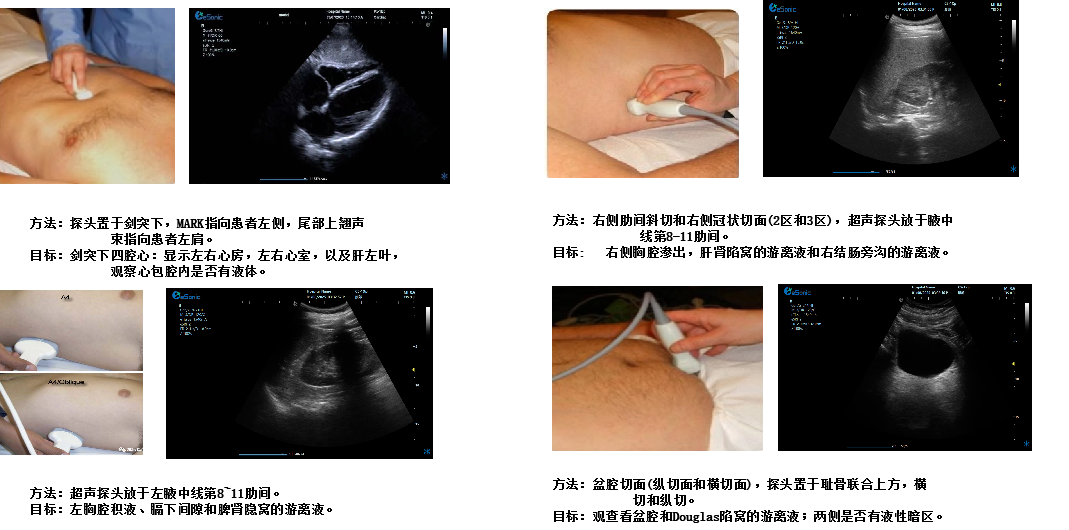

创伤评估FAST

image.png

重症肺部超声

超声声像图:声束垂直胸膜线时,可见多条A线与胸膜线平行,且等间距。

膈肌超

评估内容:膈肌移动度、膈肌厚度、增厚率。

评估意义:判断病人膈肌功能,呼吸功能,脱机前后评估等

常用检查模式:B、M

检查探头:凸阵、线阵

对超声设备要求:M型、解剖M型;测量快速准确;有专用的测量包